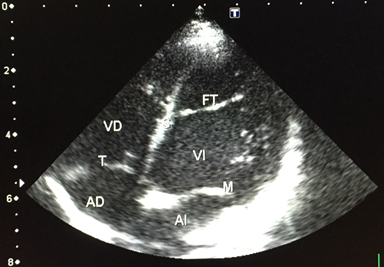

Congenital heart disease was present in 22 (52%) of the evaluated patients, with the most common defect being ventricular septal defect found in 9 (40.91%) cases Figure 1, followed by atrial septal defect in 4 (18,18%), patent foramen ovale in 3 (13.64%), and patent ductus arteriosus in 2 (9.09%) Table 2.

The associated pathologies were Trisomy 21 in six children (14,29%), and of those, four had minor cardiac defects: three had perimembranous ventricular septal defects, one had an atrial septal defect, and two did not present congenital heart disease. One child was a carrier of Seckel Syndrome, and another had an ano-rectal malformation. In three of the studied children, we found a false tendon or fibromuscular accessory in the left ventricle. They presented a systolic murmur of grade 2/6 in the mesocardium and were referred for further evaluation Figure 2.

Figure 1 FT: False fibromuscular tendon in the left ventricle.

Figure 2 Perimembranous interventricular septal defect. (+ +).